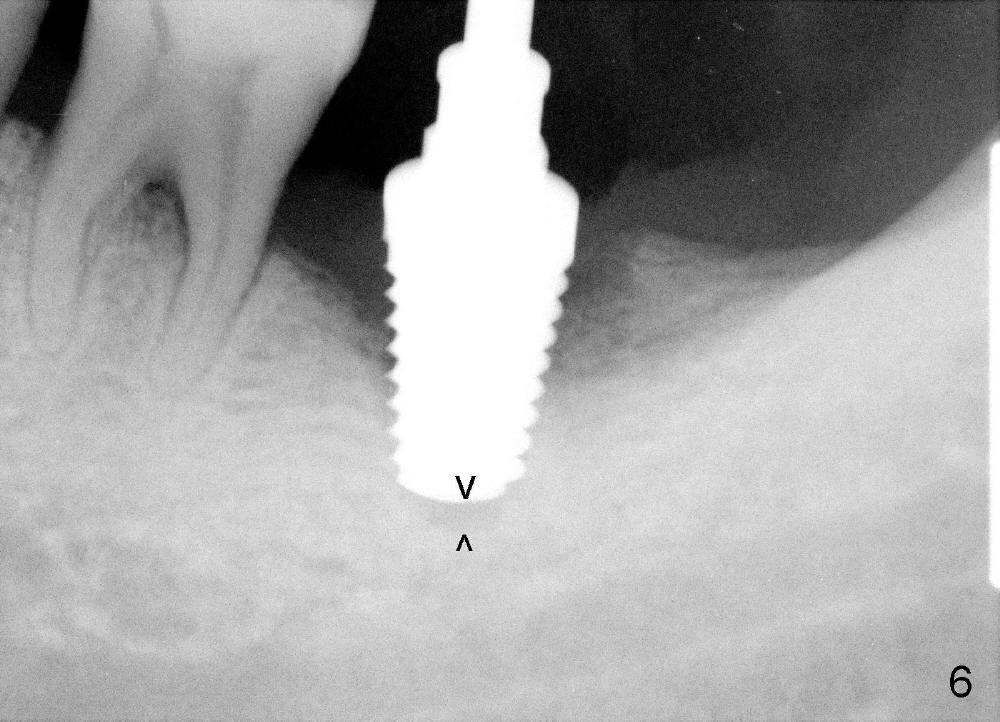

How about flatten the septum (Fig.4 white lines; from inset A (post extraction) to B)? When the septum is level with the mesial and distal sockets, a drill easily penetrates the middle of the socket (Fig.3 inset C). With strict control of depth, the osteotomy increases until a 6x14 mm tap gets initial binding to the socket (Fig.5: depth 11 mm). After increase in the depth by 1-2 mm, PA is taken with a 7x14 mm tap (Fig.6). There is a gap that the tap or the corresponding implant can engage further (between arrowheads). After increase in the diameter in the bottom of the osteotomy, a 7x11 mm implant is placed with insertion torque between 45 and 50 Ncm; the threads of the implant have tight contact with the bone (Fig.7). With the large diameter implant, the socket opening is closed without too much tension (Fig.8). The wound is protected with perio dressing. Postop there is no paresthesia. Pain is controlled by Hydrocodon/Acetaminophen. A long acting local anesthetic (Marcaine) should have been used immediately postop. Next morning, the patient is pain free. A short implant should be used in a critical area such as the lower 2nd molar where the inferior alveolar nerve is nearby. However, the implant is found unstable 1 month postop.